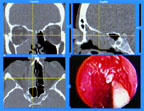

The InstaTrak display gives a 3D "road map" to surgeons by showing CT

cross sections and live video from the tip of the endoscope.

InstaTrak gives a three-dimensional "road map" to surgeons, so that they can see not only the area at the tip of the endoscope, but also the surrounding anatomy and where their surgical instruments are. Now the surgeon can see where the optic nerve lies and where the surgical instrument is in relationship to it. This computer-aided vision gives surgeons the ability to operate with greater precision, benefiting their patients.

InstaTrak uses CT scans acquired before the operation to provide the three-dimensional "road map." Patients wear a special head-set while the CT scans are taken and during the operation, so that the image data can be aligned precisely with the patientıs orientation. Before the operation, sensors are attached to the surgical instrument so that its location is tracked precisely. Endoscopic video data is also integrated in the computer system so that the surgeon can see all of the important data on screen at once.